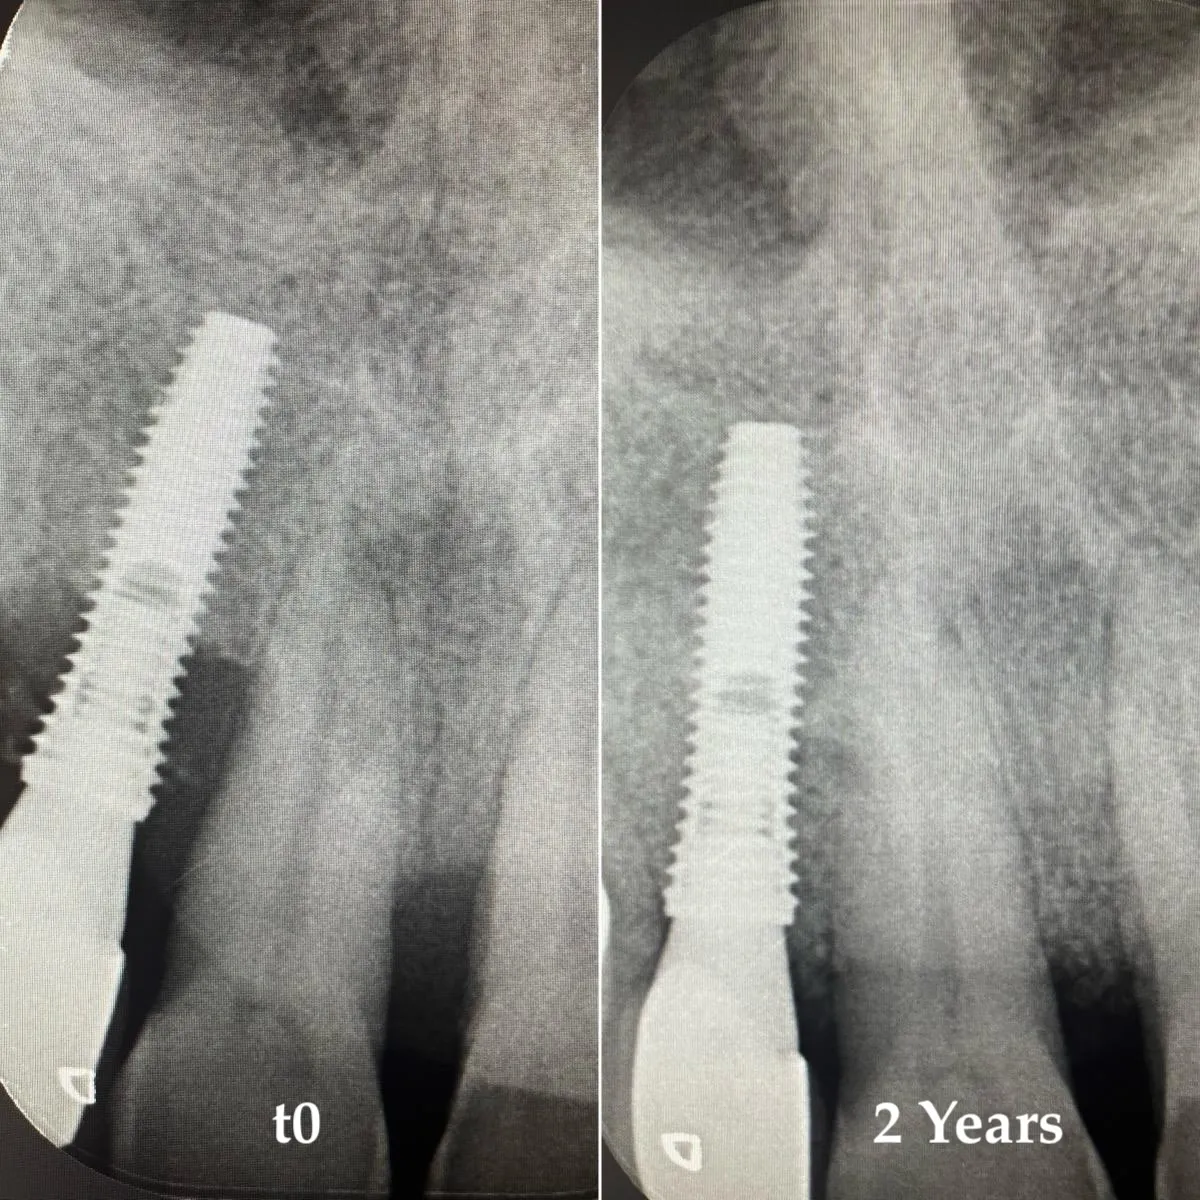

At a glance — Severe peri-implantitis at implant site 1.2 with adjacent periodontitis: combined single-session surgical treatment using TST decontamination (HybenX + air polishing) and guided bone regeneration with xenograft and porcine cortical lamina. Two-year radiographic follow-up showing documented bone fill. Clinical case by Dr. Marianna De Nale.

Periapical radiographs show documented bone fill in the peri-implant defect. No progression of bone loss. The implant remains in function.